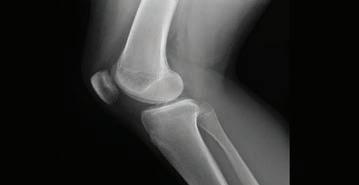

www.miraclenews.com Volume 22- Issue 585 - December 2, 2022 -Jamadiul I, 8,1444 H, $1 THE Trudeau announces $42.5 million in funding 10 terrorists killed during operation in Baloc Why the West hesitates to condemn racism? Abbotsford Islamic Centre hosts the MPs CMMC New Board Members 2023-24 Vancouver hosted its annual SKM FR. Was Napoleon a Muslim? 20 Environmental Problems That Our World 10 Osteoarthritis Symptoms 07 06 10 09 08 10 03 06 09 BC, CANADA First Muslim Biweekly & Bilingual